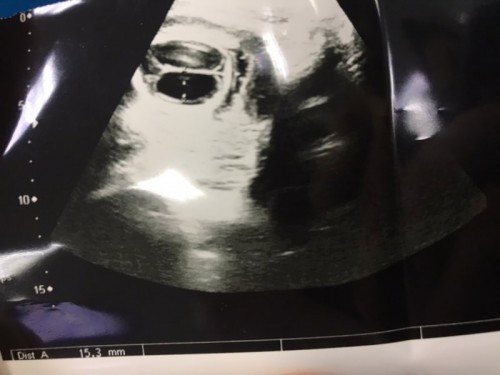

ทารกมีน้ำในโพรงสมอง

ขอคำแนะนำตอนแม่ๆท่านไหนที่เคยตรวจพบน้ำในโพรงสมองของทารกหน่อยคะ ตอนนี้เสียใจมากๆเลย น้องมีน้ำในสมองขนาด1.53cm มีทางจะหายไหมคะ ตอนนี้ได้17weedแล้ว ยังทำใจไม่ได้เลยคะ แม่มีอาการรกใหญ่ น้ำคล่ำน้อยประกอบด้วย